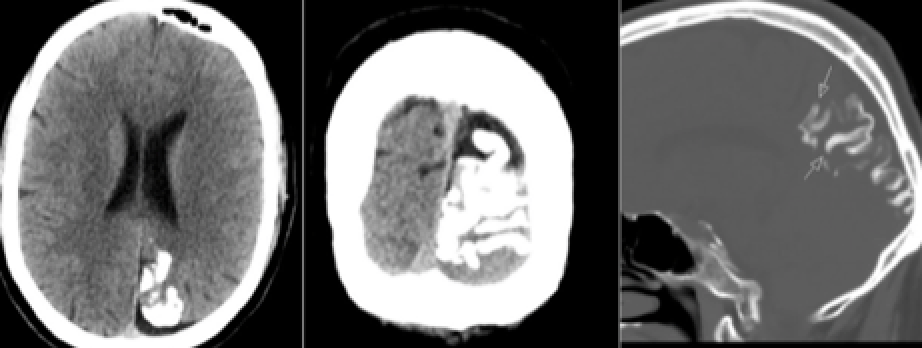

65yo man found dead in bed, wife attempts to cash in new $1 million life insurance policy hours later

Likely diagnosis?

Other considerations?

Carbon monoxide poisoning

CT: hypodense basal gangila (especially globus pallidus)

MRI: T2 bright basal ganglia, especially globus pallidus, can restrict diffusion acutely

(note also diffusely T2 dark white matter, another CO feature)

Other differential diagnoses: Cyanide poisoning (globus pallidus)

methanol toxicity or Wilson’s disease (but generally involve putamen)